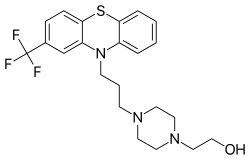

| Formula | C22H26F3N3OS |

| Molar mass | 437.53 g·mol−1 |

| |

Fluphenazine is a typical antipsychotic of the phenothiazine class.[2] Its mechanism of action is not entirely clear but believed to be related to its ability to block dopamine receptors.[2] In up to 40% of those on long term phenothiazines, liver function tests become mildly abnormal.[6]